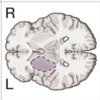

ACA Syndrome

(blue in picture)

L MCA Syndrome

(yellow in picture)

PCA Syndrome

(red in picture)